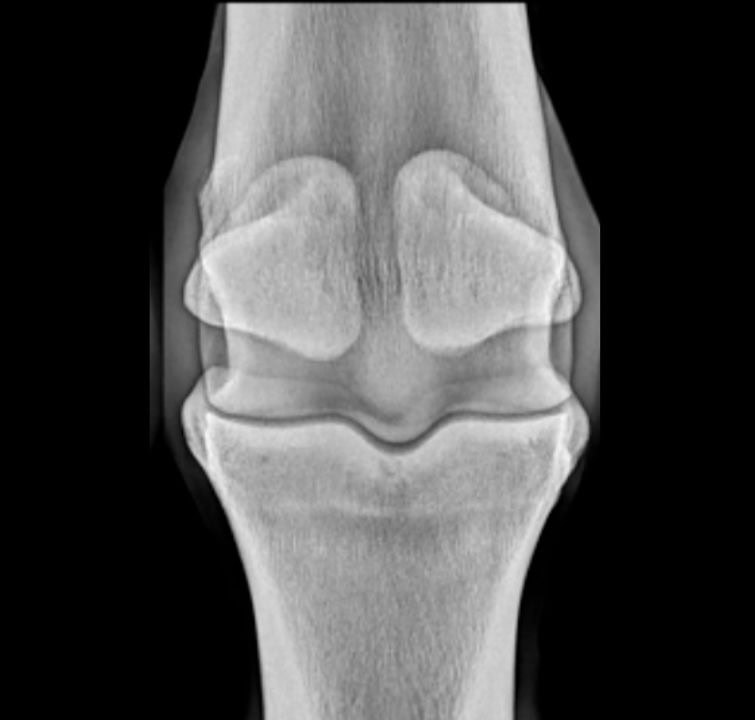

Radiology of the Fetlock and Pastern with Dr. Bri Henderson BVMS MRCVS DACVSMR

Sharpen your radiographic eye and clinical decision-making with practical tips, common pathology patterns, and image-taking techniques that reveal what other views can miss.